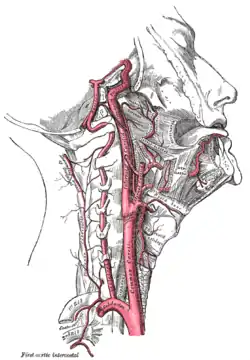

C. Nasal blood supply – arteries and veins

Like the face, the human nose is well vascularized with arteries and veins, and thus supplied with abundant blood. The principal arterial blood-vessel supply to the nose is two-fold: (i) branches from the internal carotid artery, the branch of the anterior ethmoidal artery, the branch of the posterior ethmoidal artery, which derive from the ophthalmic artery; (ii) branches from the external carotid artery, the sphenopalatine artery, the greater palatine artery, the superior labial artery, and the angular artery.

The external nose is supplied with blood by the facial artery, which becomes the angular artery that courses over the superomedial aspect of the nose. The sellar region (sella turcica, "Turkish chair") and the dorsal region of the nose are supplied with blood by branches of the internal maxillary artery (infraorbital artery) and the ophthalmic arteries that derive from the internal common carotid artery system.

Internally, the lateral nasal wall is supplied with blood by the sphenopalatine artery (from behind and below) and by the anterior ethmoid artery and the posterior ethmoid artery (from above and behind). The nasal septum also is supplied with blood by the sphenopalatine artery, and by the anterior and posterior ethmoid arteries, with the additional circulatory contributions of the superior labial artery and of the greater palatine artery. These three vascular supplies to the internal nose converge in the Kiesselbach plexus (the Little area), which is a region in the anteroinferior-third of the nasal septum, (in front and below). Furthermore, the nasal vein vascularisation of the nose generally follows the arterial pattern of nasal vascularisation. The nasal veins are biologically significant, because they have no vessel-valves, and because of their direct, circulatory communication to the cavernous sinus, which makes possible the potential intracranial spreading of a bacterial infection of the nose. Hence, because of such an abundant nasal blood supply, tobacco smoking does therapeutically compromise post-operative healing.